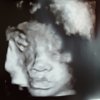

Altfor sent til å få bra bilder med 3d?? Jeg var på 3d i forrige uke (32+3 da) og jeg fikk kjempe bra bilder. Han anbefalte ikke å komme så seint, om det skulle bli noe neste gang. Men sa det var best resultat i uke 28/29. Så det var dårlig av Hu dama som tok ul på deg syntes jeg! :/3d ultralyd av jenta vår i dag. 29 +1.

Sur dame som mente det var jo alt for sent til å få ok bilder nå! Dette var det beste og eneste jeg fikk. ( er ikke en utvekst på hodet der altså)

Men må innrømme jeg er skuffa når jeg ser hvor fine bilder dere andre har fått i samme uka... :-/